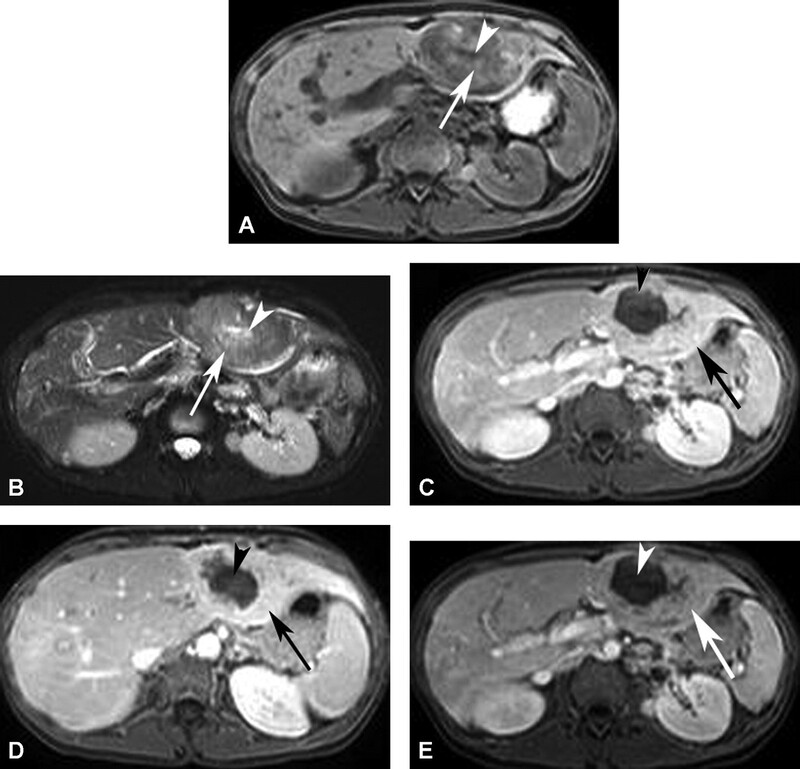

Trên CT không cản quang, HCC thường giảm đậm độ so với gan. HCC bắt quang thì động mạch và trở nên giảm đậm độ ở thì tĩnh mạch cửa (Hình 10). Viền bắt quang mỏng có thế có ở thì tĩnh mạch và thì muộn do giả bao. Thực hiện thì động mạch trễ (34 giây) đã được báo cáo cho thấy các nốt HCC hơn thì động mạch sớm (20 giây). Các hình thì động mạch sớm có khả năng chụp mạch CT 3D chất ợng tốt hơn để lập bản đồ mạch máu trước phẫu thuật. Thêm hình ảnh CT thì muộn (180 giây) đã được báo cáo để cải thiện độ nhạy và độ đặc hiệu trong phát hiện HCC so với CT hai pha.

Nói chung, HCC tăng tín hiệu trên T2W và giảm tín hiệu trên T1W. Hình MRI sau tiêm thuốc thấy bắt thuốc thì động mạch rõ rệt, không đều, thải thuốc nhanh ở thì tĩnh mạch và thì muộn (Hình 11). Phát sinh bắt thuốc viền ngoại vi do giả bao. Nốt loạn sản độ cao có thể bắt thuốc. Tuy nhiên, nốt loạn sản không có bao giả. HCC lan tỏa có tín hiệu không đồng nhất trên T1W và T2w, với bắt quang không đều, có các vùng thải thuốc và các vùng khác có thể còn đọng thuốc. Huyết khối do u ở tĩnh mạch cửa cho thấy bắt quang ở thì động mạch điển hình (Hình 10 và 11). Dấu hiệu này giúp phân biệt huyết khối do u với huyết khối lành tính, không bắt quang ở thì động m ạch. Bao u có thể thường gặp ở người châu Á, là các viền echo trống trên siêu âm và bắt thuốc viền ngoại vi ở thì trễ trên CT và MRI.

Hình 10. Bệnh nhân nam 62 tuổi xơ gan và carcinoma tế bào gan thâm nhiễm lan tỏa. CT không cản quang (A) thấy bờ ngoài gan dạng nốt kèm khối giảm đậm độ (mũi tên) ở thùy gan phải. CT thì độn g mạch (B) thấy khối bắt quang không đồng nhất (mũi tên). Huyết khối do u bắt quang không đồng nhất (mũi tên ở C) làm phình lớn tĩnh mạch cửa và lan đến chỗ hợp lưu tĩnh mạch mạc treo tràng trên (mũi tên ở D). U đồng đậm độ (mũi tên) với gan do thải thuốc ở thì tĩnh mạch cửa (E).

Hình 11. Bệnh nhân nam 62 tuổi xơ gan và carcinoma tế bào gan thâm nhiễm lan tỏa (cùng bệnh nhân ở hình 10). Khối giảm tín hiệu (mũi tên) trên hình T1W 3D GRE (A) và tăng tín hiệu (mũi tên) trên hình T2W SSFSE (B). Khối bắt thuốc không đồng nhất (mũi tên) ở thì động mạch với bờ lan tỏa (C). Huyết khối do u bắt thuốc không đồng nhất (D, mũi tê n) phình lớn tĩnh mạch cửa và lan vào hợp lưu tĩnh mạch mạc treo tràng trên (E, m ũi tên). Thì muộn (F) thấy u thải thuốc kèm bắt thuốc vách bên trong (mũi tên) và giả bao.